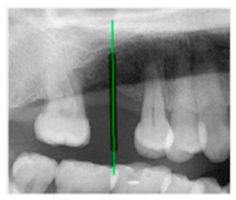

| AI-assisted and implant path visualization result | ||||||

| Validation Image 1–6 | ![]() | ![]() | ![]() | ![]() | ![]() | ![]() |

| Comparison with dentist’s ground truth (black line) and our framework (green line) | ||||||

| MSE | 3.59 | 1.29 | 0.41 | 0.80 | ||